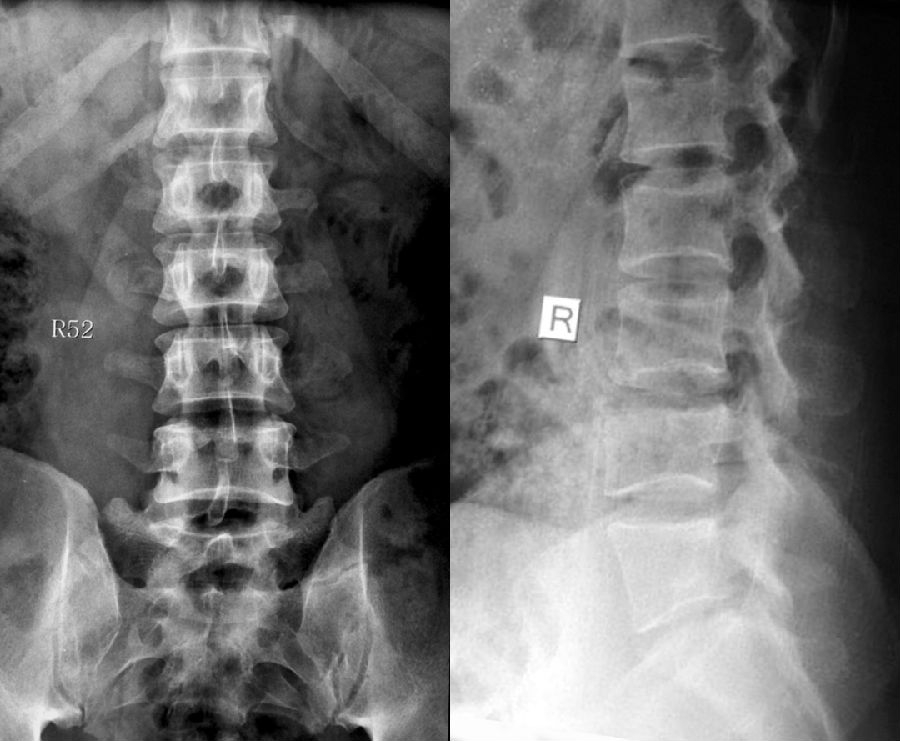

1984年,Castellvi提出LSTV分类系统将移行椎分为Ⅰ-Ⅳ型。

Ia型(单侧)和Ib型(双侧):横突肥大宽度超过19mm

IIa型(单侧)和IIb型(双侧):横突与骶骨相接触形成假关节

IIIa型(单侧)和IIIb型(双侧),横突与骶骨发生骨性融合

IV型:一侧横突与骶骨形成假关节,另一侧形成骨性融合

目前,腰骶移行椎以Castellvi的分类方法最为常用。其主要根据横突形态及其与骶骨、髂骨是否融合或形成假关节而分为4型,Ⅰ、Ⅱ、Ⅲ型又根据单、双侧分为A、B两个亚型。

正常

I型:主要为腰5横突发育不良,横突宽度大于19mm,并将其分为两个亚型Ia(单侧横突发育不良)或Ib(双侧横突发育不良)

L5右侧横突肥大,为Ⅰa型

L5双侧横突肥大,为Ⅰb型

II型:表现为不完全的腰椎骶化,具有增宽的横突,并且和骶骨形成假关节,并将其分为两个亚型IIa(单侧关节形成)或IIb(双侧关节形成)

L5左侧横突肥大,假关节形成,为Ⅱa型

L5双侧横突肥大,假关节形成,为Ⅱb型